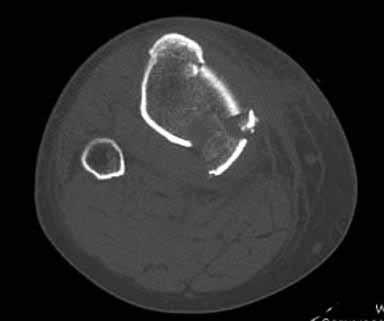

Здравствуйте уважаемые коллеги!Сегодня обратился больной 35л. Травму получил 3 мес.назад, упал в яму, лечился в отдаленном районе гипсовой повязкой, 1 месяц назад гипс сняли , и больной начал ходить с нагрузкой, постепенно появилась деформация коленного сустава, неустойчивость и боли. Локально: деформация коленного сустава, голень смещена кзади- типа подвывиха, разгибание 170гр. Сгибание 150гр.симптомов повреждение коллатеральных и крестообразных связок определить не удается из-за боли и контрактуры. Первичных снимков пока нет, обещали принести, имеется снимки через 2 месяца после травмы без гипса, недельной давности снимки в прямой проекции и К Т. Похоже, что импрессия переднемедиальной части внутреннего мыщелка б/берцовой кости, отрыв межмыщелкового возвышения.

На снимке типичный перелом медиального тибиал плато с передним смещением (подвывих) по Schatzker IV. Консервативное лечение без медиальной опоры не может удержать деформирующие силы, и из-за вторичного смещения мыщелка конечность смещается в варус. Кроме передних смещений еще встречаются сложные фронтальные варианты переломов, и тогда голень подвывихивается кпереди.

А в данном случае мыщелок сросся со смещением кпереди и ротирован. За счет интактной наружной колонны опороспособность конечности сохранена, но остается варус и экстензия конечности. Для предоперационного расчета необходимо сделать на всю длину конечности рентгенограмму, а в остром периоде КТ и 3-мерный снимок помогут лучше ориентироваться в характере перелома.

Остеотомия с разворотом медиального мыщелка, и для фиксации можно применить параллельные субхондральные межмыщелковые шурупы. Дополнительная медиальная Smith-Nephew PERI-LOC™ (Periarticular Locked Plating System) пластина. При отсутствии специальной пластины можно адаптировать Tomofix для высокой остеотомии. Доступ прямой медиальный через pes anserinus или через интервал pes с medial gastrocnemeus.